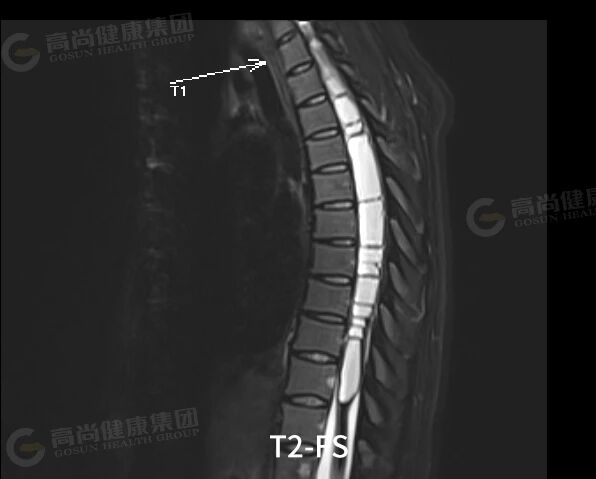

延髓水平至 T12 椎体水平椎管内可见分布大小不等囊状信号,C2 椎体下缘水平至 C7 椎体水平下缘髓内可见长 T1、混杂长 T2 信号,病灶两端见弧形低信号,T2 压脂示病灶内散在结节状稍高信号,横轴位见肿块位于脊髓中央,正常脊髓显示不清,增强扫描呈轻中度不均匀强化,范围约 73 mm×15 mm。

结论:颈髓内占位伴广泛性脊髓囊样改变,考虑室管膜瘤伴脊髓空洞可能。

1. 部位与形态: 位于髓内,常呈边界清晰的梭形或腊肠形肿块。肿瘤常位于脊髓中央,可对称性或轻度偏心性生长。约 20-50% 的病例,肿瘤头端和/或尾端可出现囊变,这些囊腔通常为非肿瘤性的脊髓软化或空洞。

T2 加权像: 呈不均匀高信号。两个特征性征象具有较高诊断提示价值:

「帽征」: 在肿瘤两极的 T2WI 上常见低信号「帽」,为含铁血黄素沉积,源于肿瘤易出血的特性。